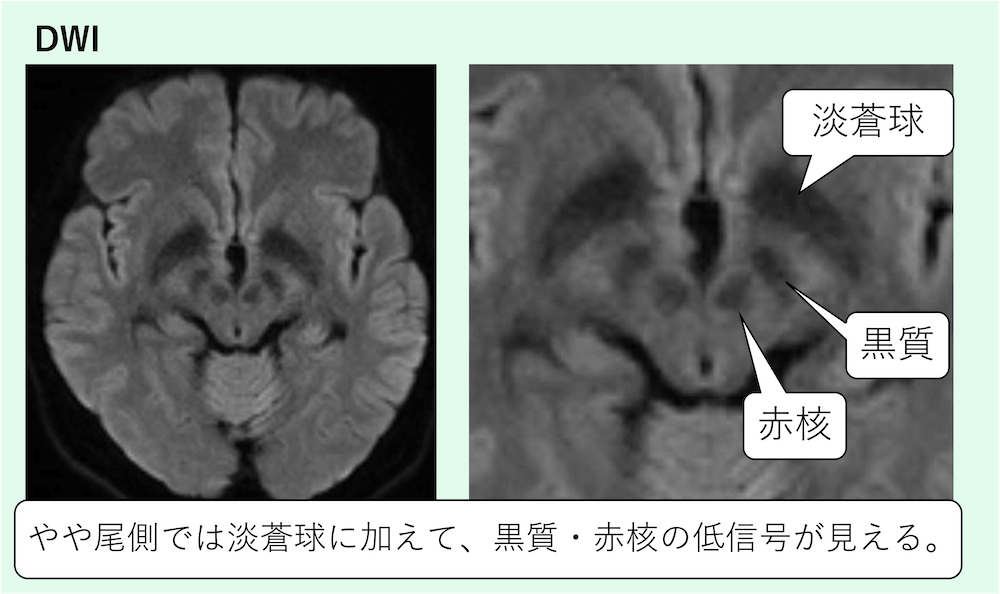

やや尾側では淡蒼球に加えて、黒質・赤核の低信号が見えます。

中脳レベルでは赤核の低信号が見えます。